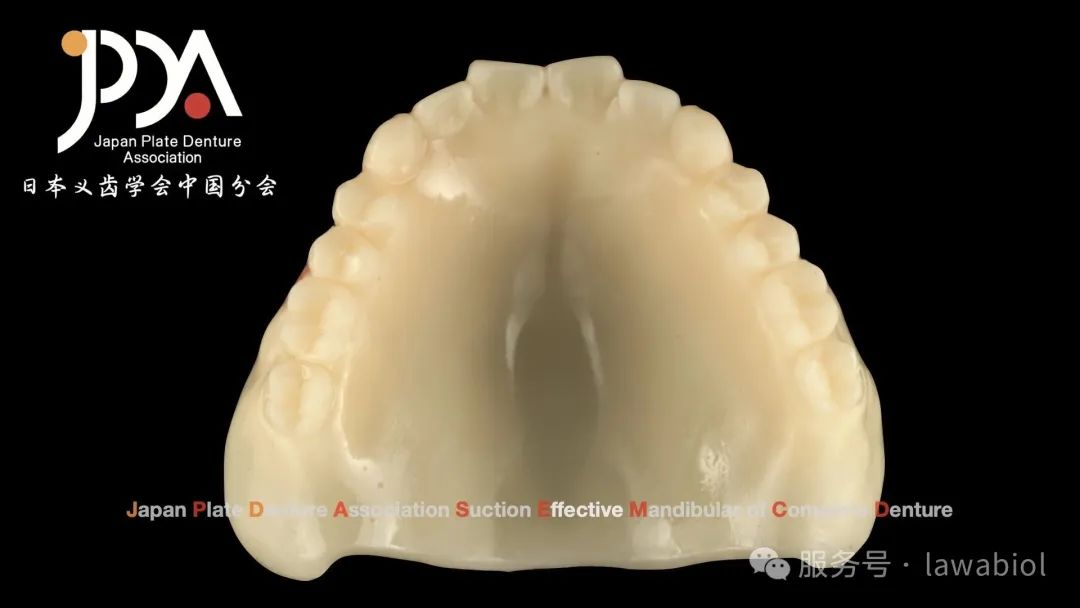

杭州拉瓦与爱迪特共同推出的"数字化全口整体解决方案"成为会议焦点。现场通过数字化3D打印技术,演示了"一体式"与"分体式"过渡义齿的制作过程,精准适配复杂牙槽嵴形态。

佐藤勝史先生为日本患者试戴过渡义齿后,拉瓦基于试戴数据,使用数字化切削设备实时完成终义齿制作,完整呈现了数字化"即刻修复"的全流程。拉瓦展台展出的数字化解决方案以其精准度和高效性,吸引了众多参会者交流探讨。